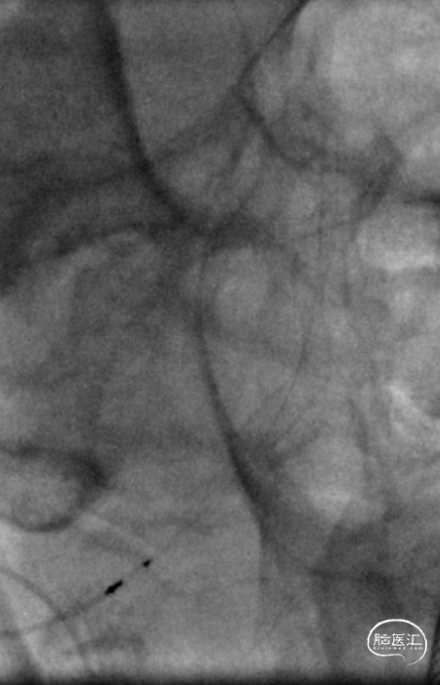

术后即刻DSA。

术后即刻稀释造影:“拉直”可见支架贴壁良好。